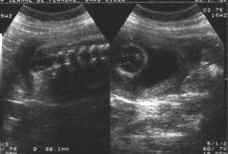

- Coupes frontales :

Ecartement des lames postérieures responsables de la perte de parallélisme du "rail spinal".

cliché droit

cliché gauche

Affleurement et renflement anormal du canal rachidien qui perd son caractère linéaire (collet herniaire).

En dehors du rachis, tuméfaction (hernie) mobile avec le foetus.